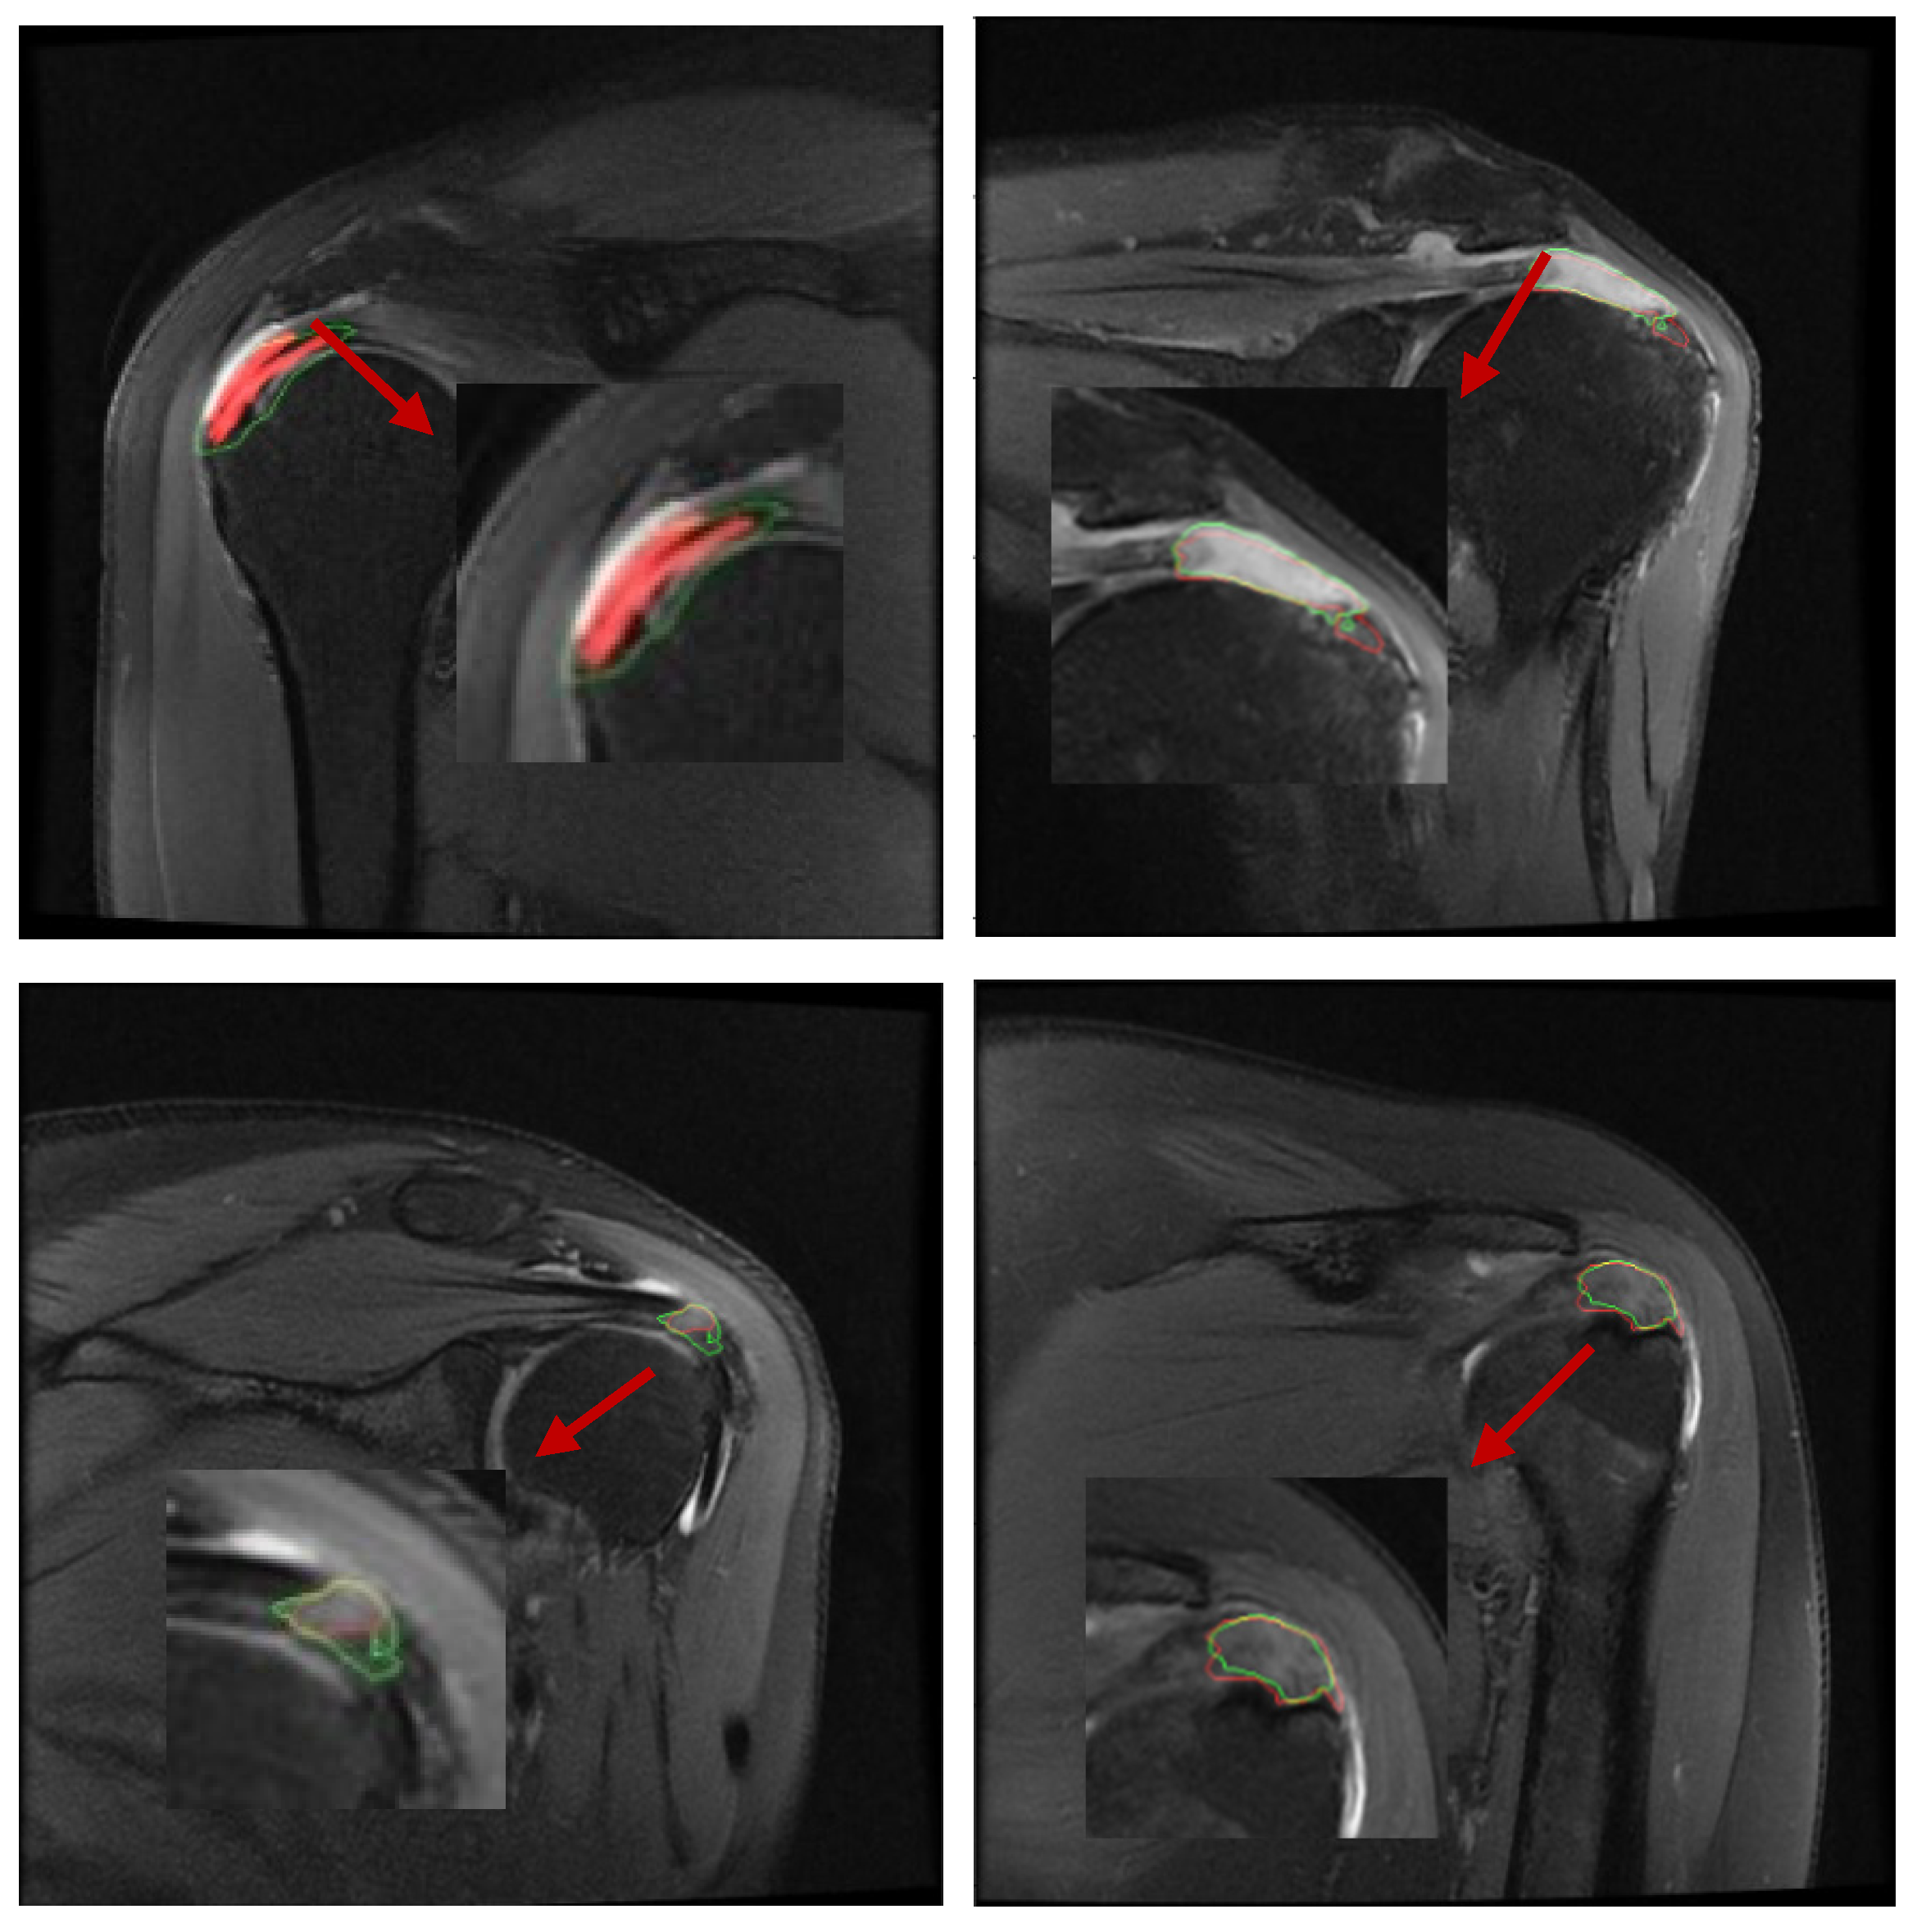

In the clinical diagnosis of rotator cuff tears nowadays, doctors often need to take a close look at multiple MRIs of the shoulder and combine them into a coherent sequence of MRIs to determine whether the area of the lesion is an effusion or a tear [4], and to measure the length of the tear with calipers to give the grade of the tear (Figure 1). The AI diagnostic method proposed in this paper can assist doctors to greatly improve the diagnostic efficiency, which has many advantages over traditional clinical diagnosis.

2.2. Image Acquisition: Ocor T2 fs Sequence

The data used in this study were MRI scan sequence images of patients (device GE HealthCare, 3.0T MR750 WIDE, GE HealthCare, Beijing, China). Each sequence consisted of 15~20 2D images. The size of the images was 320 × 224 (pixel), the field of view (FOV) was 16 × 16 (cm), the thickness was 3 mm, and the interval between images was 0.5 mm [5]. For each patient, it is often necessary to take multiple sequences because of the problem of moving during image acquisition, from which the most clearly imaged set of sequences was then selected as the data for training. Figure 1 shows examples of the workflow.

Figure 1. A typical tear image of Ocor T2. The arrow shows that the tendon is retracted from point a to point b after rupture, and the joint fluid-filled area is visible in the highlighted area between point a and point b. The joint fluid-filled area is the tear region.